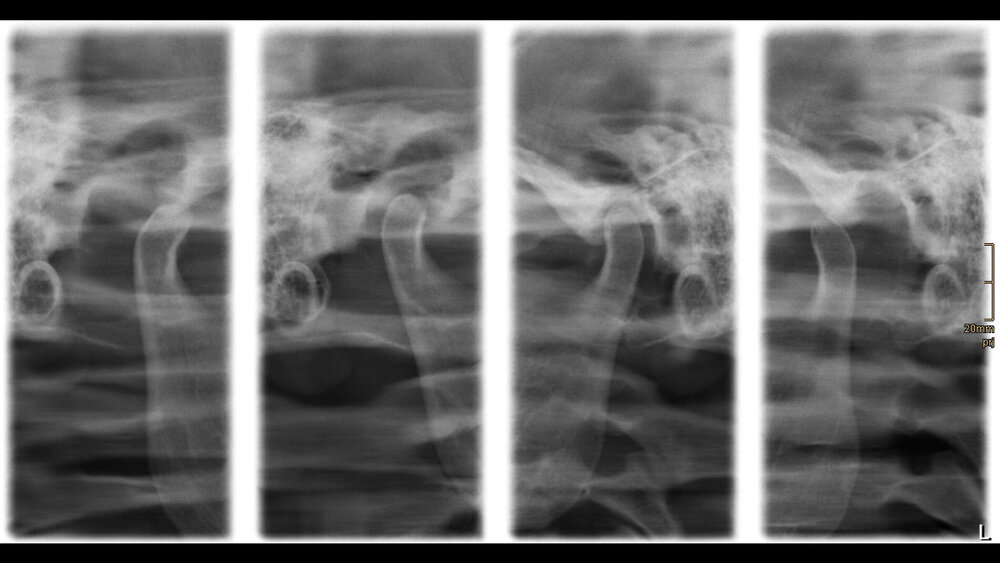

Zufallsbefund eines Riesenzelltumors bei langjähriger Bruxismus-Patientin